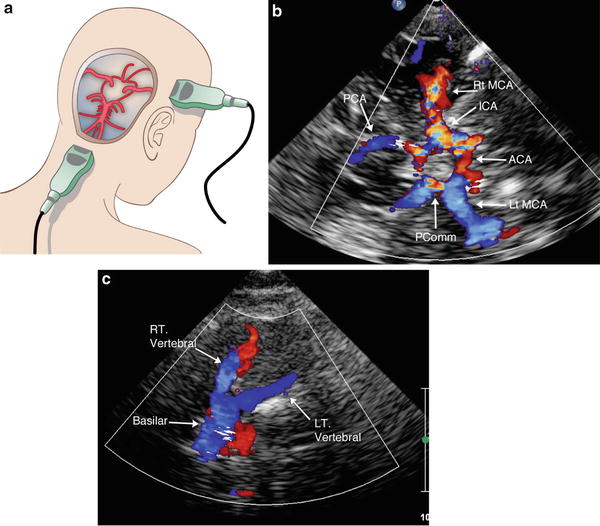

Pediatric applications of transcranial doppler sonography

Application Of Transcranial Doppler Ultrasound In Pediatric - Application Of Transcranial Doppler Ultrasound In Pediatric

Doppler Sonography Of The Brain In Children - Doppler Sonography Of The Brain In Children